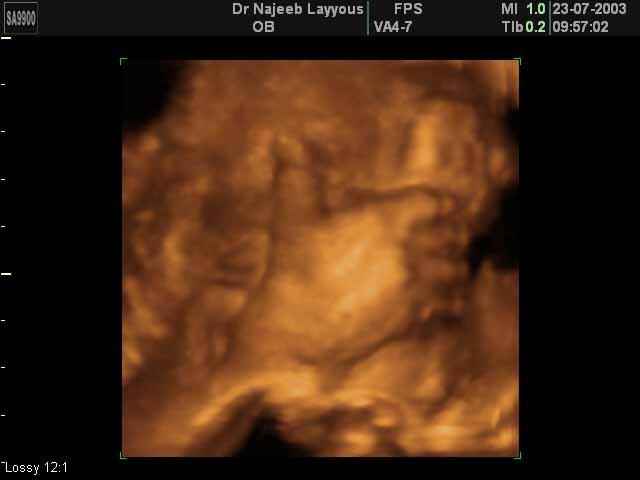

- تصرفات الجنين داخل الرحم

- صور لأطراف الجنين

- صور لتصرفات الجنين داخل الرحم